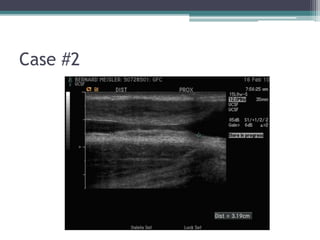

Case #2

โ€ข 67 M undergoing spinal surgery โ€“ unable to

place foley catheter

โ–ซ Urology consulted โ€“ cystoscopy performed, unable

to place wire into bladder b/c of urethral stricture

โ–ซ SP tube placed

โ€ข Lumen size estimated to be

around 8-10 F

โ€ข Length โ€“ 3 to 4 cm

โ€ข Options?

โ–ซ EPA

โ–ซ Graft

โ–ซ Flap